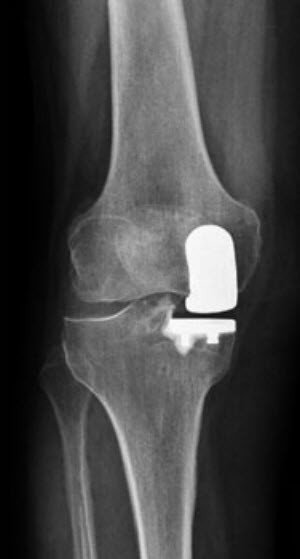

Ist von der Abnutzung nur der Kniescheibenteil oder der innere oder äussere Teil des Kniegelenks betroffen, kann ein teilweiser Gelenkersatz (Schlittenprothese / unikompartimentelle Kniearthroplastik) eingesetzt werden. Wichtige Voraussetzungen für die Indikation sind, dass sich die Arthrose hauptsächlich auf einen Abschnitt des Kniegelenks beschränkt und dass die Kniebänder noch funktionell sind.

Eine Teilprothese bietet im Vergleich zur Totalprothese grösstenteils eine bessere Beweglichkeit sowie ein natürlicheres Kniegefühl. Der Eingriff ist ausserdem weniger invasiv, da alle Bandstrukturen und die noch gesunden Gelenkteile erhalten bleiben, was die rasche Erholung nach der Operation begünstigt.